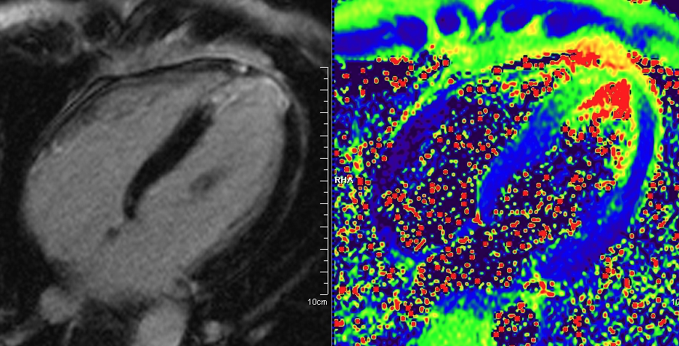

- Technische Innovationen: Ödembildgebung, Mapping, Koronararterien

- Technische Innovationen: (Ergänzung) Funktion, Late Gadolinium Enhancement